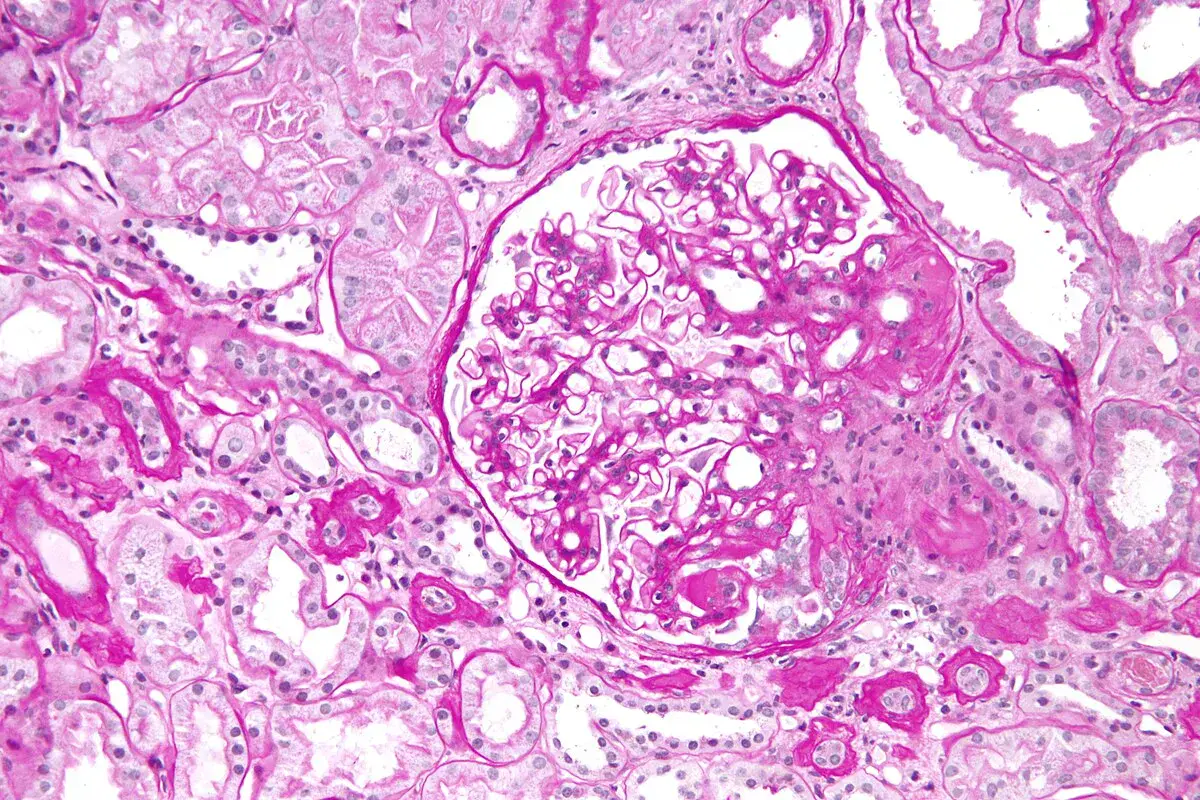

Doador vivo: quais critérios clínicos importam no aconselhamento pré-doação em mulheres com desejo de gestar?

Doação renal em mulheres jovens pode impactar mais o feto do que a mãe — e esse dado muda o pré-operatório. O maior estudo já feito mostra aumento de PIG e sinais de disfunção placentária silenciosa, especialmente em nulíparas. Se você ainda não discute isso de forma explícita no consentimento, talvez esteja subestimando o risco.